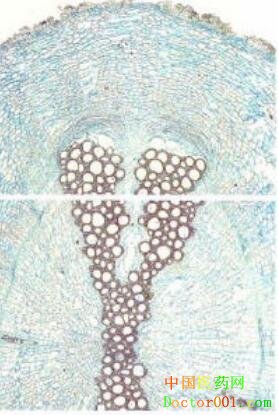

【標題】 青木香 【拼音】 Qingmuxiang 【概述】 為馬兜鈴科植物馬兜鈴Aristolochia debilis Sieb.et Zucc.的干燥根。主產于江蘇、浙江、安徽等地。春、秋二季采挖,除去須根及泥沙,曬干,切片。生用。 【性味歸經】 辛、苦,寒。歸肝、胃經。 【功效】 行氣止痛,解毒消腫。 【應用】 1.胸脅、脘腹疼痛。本品辛行苦泄,主入肝胃經,能行氣疏肝,和中止痛。治療肝胃氣滯的胸脅脹痛,脘腹疼痛,單味服用即有效,或與香附、川楝子、佛手等同用。 2.瀉痢腹痛。本品苦寒,清熱解毒辟穢,味辛行氣止痛。可取鮮品搗汁服或干品研末服,或與葛根、黃連、木香等配伍,用治夏令飲食不潔,暑濕內阻所致瀉痢腹痛。 3.疔瘡腫毒,皮膚濕瘡,毒蛇咬傷。本品苦寒,有清熱燥濕,解毒消腫之功。治疔瘡腫毒,可單味研末,水蜜調敷,或以鮮品搗敷;若治皮膚濕瘡,可取本品煎水外洗,并研末外撒,或配伍明礬、五倍子、爐甘石等;治毒蛇咬傷,則每與白芷配伍,內服并外用,或與穿心蓮、蚤休等同用。 【注意】 本品不宜多服,過量可引起惡心、嘔吐等胃腸道反應。 【用法用量】 煎服,3~9g。散劑每次1.5~2g,溫開水送服。外用適量,研末敷患處。 【臨床研究】 1.化學成分:本品含揮發油,油中主要成分為馬兜鈴酮,并含馬兜鈴酸、青木香酸,木蘭花堿、尿囊素、土青木香甲素及丙素等。 2.藥理作用:青木香煎劑對多種原因引起的高血壓有明顯的降低血壓作用,其所含木蘭花堿對腎性高血壓的降壓作用明顯;青木香總堿對金黃色葡萄球菌及綠膿、大腸、變形等桿菌有不同程度的抑制作用;馬兜鈴酸有提高機體免疫功能的作用,并能增強腹腔巨噬細胞的吞噬活性;研究證實,馬兜鈴酸有一定的致突變和致癌作用。 3.臨床研究: 用青木香精制浸膏片(每片相當生藥6g),每次4~12片,每日3~4次,治療Ⅱ期高血壓有療效,收縮壓下降較舒張壓下降明顯(中藥藥理與臨床應用,人民衛生出版社,1982:19);單味青木香顆粒治療幽門螺旋桿菌感染胃炎患者30例,并與西醫三聯療法治療此病患者30例作對照,4周為1個療程。結果2組臨床有效率、HP清除率比較基本近似,但HP根除率青木香組(86.4%)較高于三聯組(68.0%),P<0.05,有顯著性差異,服藥期間青木香組無1例有不良反應 (安徽中醫臨床雜志,1998,6:352);用青木香20g,地錦草100g水煎服,治療細菌性痢疾,有較好療效(四川中醫,1990,1:31);以青木香在患處局部外用,治療五官科急性炎癥148例,治愈113例,總有效率92.6%(福建中醫藥,1958,2:33)。另有單用青木香治療潰瘍病、胃炎、胃痙攣及其他原因引起的胃痛,以青木香局部外用治療五官科急性炎癥等。 4.不良反應:有報道嚼服鮮青木香約150g引起中毒,開始惡心嘔吐,食入即吐,繼則尿少,腹脹肢腫,導致急性腎功能衰竭、尿毒癥。(江西中醫藥,1995,2:25)。口服大量青木香流浸膏可見惡心嘔吐,胃納減退,口干,便秘等;靜脈注射可出現全身痙攣,瞳孔先大后小,肌肉松弛,呼吸抑制,最后心跳停止。中毒原因主要為治療用量過大;中毒預防首先不宜用注射劑,其次是口服劑量也不可過大。中毒救治:中毒較輕者,停止用藥,多可緩解;中毒較重,視情況隨癥處理,如出現呼吸麻痹,可進行人工呼吸、氣管插管等。 【參考文獻】 1.《新修本草》:“主積聚,諸毒熱腫,蛇毒”。 2.《本經逢原》:“治癰腫,痰結、氣凝諸痛。” 3.《本草求真》:“青木香,諸書皆言可升可降,可吐可利。凡人感受惡毒,而致胸脯不快,則可用此上吐,以其氣辛而上達也。感受風濕而見陰氣上逆,則可用此下降,以其苦能泄熱也。” 【圖片】 藥材青木香 ![]() 藥材青木香橫切面 ![]() 青木香 馬兜鈴《中國藥典》 ![]() 馬兜鈴《本草綱目》 ![]() (責任編輯:Doctor001) |